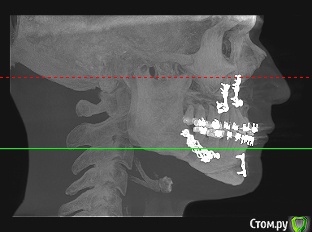

Silver80 Опубликовано 11 марта, 2018 Автор Поделиться Опубликовано 11 марта, 2018 у этих систем минимальный диаметр 3.5, у вас такая ситуация, где каждые 0,5мм - важны. Грубо говоря эти 0,5 мм - это ваша сохраненная (не высверленная под имплантат) кость, которую очень важно сохранить у соседних зубов, как для эстетики, так и для функции.8ки надо удалить.Bier , большое спасибо, что отвечаете. Меня еще мучает вопрос - можно ли как-то ортопедически скорректировать наклон передних резцов? просто я прям чувствую. как нижние зубы давЯт на верхние и боюсь, что они их вконец расшатают и вывихнут. еще опасаюсь что будет такое же давление на импланты после их установки вместе с коронкой. я просто в полной прострации щас нахожусь. 4 года лечения и понимаю, что результат всего этого не совсем тот, который бы хотелось. и ОП теперь не переделаешь. что можно сделать, чтоб и фронт был красивым и наклон и давление этих зубов изменить (на ум приходит поднятие высоты на всех жевательных зубах, но это прям совсем крайняя мера для меня, очень бы не хотелось трогать здоровые зубы под коронки). дайте совет - что делать в этой ситуации. мб что-то ортодонта попросить еще скорректировать? вот ТРГ последнее Ссылка на комментарий

Bier Опубликовано 12 марта, 2018 Поделиться Опубликовано 12 марта, 2018 Bier , большое спасибо, что отвечаете. Меня еще мучает вопрос - можно ли как-то ортопедически скорректировать наклон передних резцов? просто я прям чувствую. как нижние зубы давЯт на верхние и боюсь, что они их вконец расшатают и вывихнут. еще опасаюсь что будет такое же давление на импланты после их установки вместе с коронкой. я просто в полной прострации щас нахожусь. 4 года лечения и понимаю, что результат всего этого не совсем тот, который бы хотелось. и ОП теперь не переделаешь. что можно сделать, чтоб и фронт был красивым и наклон и давление этих зубов изменить (на ум приходит поднятие высоты на всех жевательных зубах, но это прям совсем крайняя мера для меня, очень бы не хотелось трогать здоровые зубы под коронки). дайте совет - что делать в этой ситуации. мб что-то ортодонта попросить еще скорректировать? вот ТРГ последнееПо этому вопросу лучше все же консультироваться с ортодонтами и ортогнатическими хирургами. Не моя область. Ссылка на комментарий